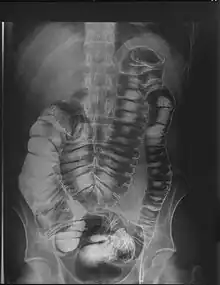

Megacólon é um transtorno intestinal caracterizado por dilatação anormal do intestino grosso, definida em um adulto como mais de 12cm de diâmetro no ceco, maior que 8cm no cólon ascendente ou descendente ou 6,5cm no cólon sigmoideo ou reto. [1]